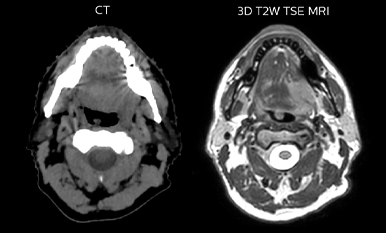

While CT clearly defines bone and cartilage, the modality’s limited soft tissue visualization makes head-and-neck structures often appear virtually indistinguishable from another. Coregistering an MRI dataset as a secondary information source for head-and-neck target and organ at risk (OAR) delineation is vital, according to La Tour’s Dr. Breuneval.

“MRI contributes substantially to visualizing head-and-neck lesions compared to CT and allows a better differentiation of normal from abnormal tissue,” he explains. “Tumor edges and extracapsular lymph node extension – as well as OARs, such as parotid glands, pharyngeal muscles and the brachial plexus – are better depicted. The resulting benefit is that tumor margins may be reduced and OARs better spared.”

Epidermoid carcinoma of the left tongue base

The patient was diagnosed with an epidermoid carcinoma of the base of the left invading the amygdala lodge and the amygdaloglossal groove. Radiochemotherapy with curative aim was prescribed with a dose of 70 Gy for the tumor, 66 Gy on the suspicious nodes and 56 Gy on the elective drainage areas - in 33 fractions.

Comparison of CT simulation scan (left) and T2W 3D MRI (right)